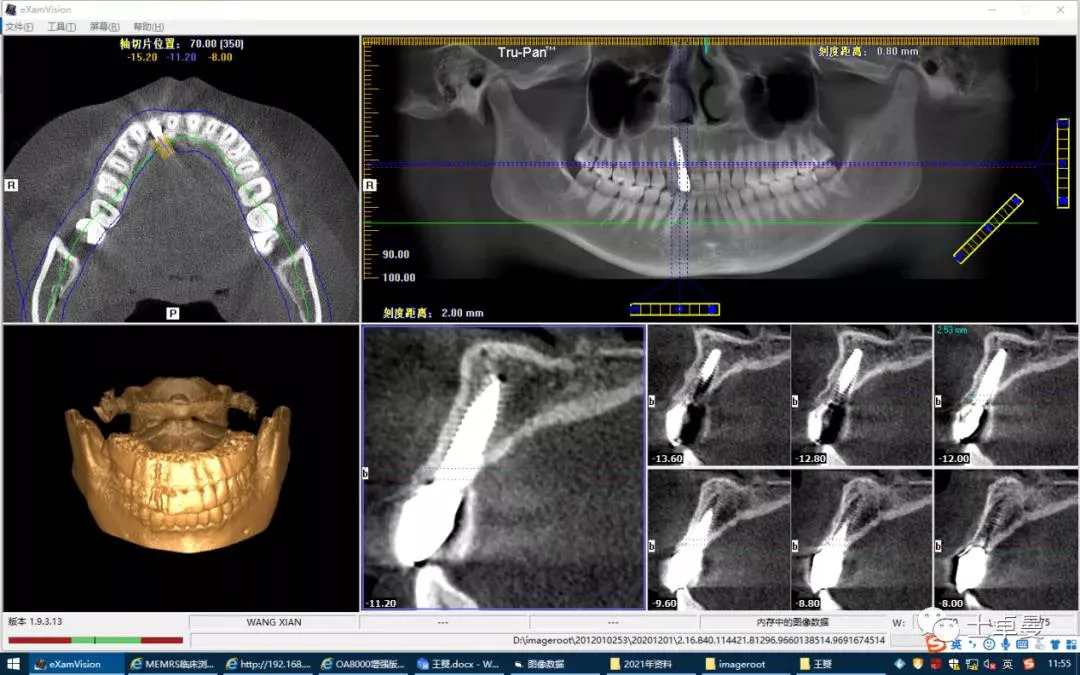

·        CBCT显示种植体三维位置良好;

术后 CBCT 显示种植体三维位置良好

·       12 断根,根尖区剩余骨高度充足,可用骨高度19mm,骨宽度7.2mm。

术前 CBCT